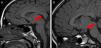

En la resonancia magnética (RM) cerebral se objetiva HH pedunculado de 11mm en el paciente 1, de 8mm en el paciente 2 y de 17mm en el paciente 3, todos ellos localizados en el tuber cinereum (fig. 1). En los 3 casos la respuesta a análogos de GnRH ha sido satisfactoria.

En la RM cerebral se visualiza HH de 1,3cm localizado entre los cuerpos mamilares (fig. 2). El cribado de pubertad precoz fue negativo.